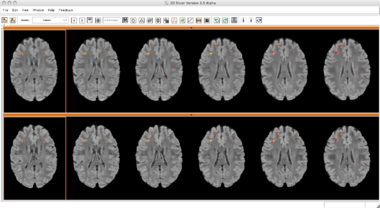

Slicer3 Module Lesion Classification

Lesion Classification Result

CompareViewFlairLesionDiffWholeBrain

CompareViewFlairLesionDiffWControls